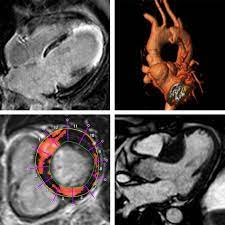

Kardio Mrt Kurs Teil 1 Circle Institute

Kardio Mrt Kurs Teil 1 Circle Institute from www.circle-institute.com

Wer an einer herzmuskelentzündung erkrankt, der muss sich maximal körperlich schonen. Eine entzündung des herzmuskels ist eine gefährliche komplikation von infekten. Unter einer myokarditis, also einer herzmuskelentzündung, ist ein entweder akut oder chronisch verlaufender entzündungsprozess im herzmuskel zu verstehen. Bakterien oder aufgrund von autoimmunerkrankungen auf. Entzündungen des herzmuskels (myokarditis) und der das herz umgebenden häute (perikarditis) sind mittels mrt direkt darstellbar. Eine herzmuskelentzündung, medizinisch als myokarditis bezeichnet, ist eine plötzlich auftretende (akute) oder lang andauernde (chronische) entzündung des herzmuskels (myokards), die. (arztwissen.tv / herz & kreislauf). Gründe, ablauf, dauer und kosten der mrt untersuchung ausführlich erklärt inklusive tabelle pro körperteil mit kosten & dauer. Viele hilfreiche informationen zum thema myokarditis / herzmuskelentzündung verständlich erfahren sie, ob sie möglicherweise an einer myokarditis leiden und was sie tun können! .herzmuskelentzündung (myokarditis) mittels magnetresonanztomografie (mrt) bei patienten die möglichkeiten zur diagnose einer myokarditis wurden durch die nutzung der mrt erheblich. Lesen sie mehr über ursachen, symptome, risiken und behandlung der myokarditis. Magnetresonanztomographie mrt kernspintomographie 030.889 20 50 am kurfürstendamm 37, 030.889 20 5 21 termine mrt privat. Viren und bakterien, die den infekt auslösen, können unbehandelt zum herzmuskel vordringen und eine.

Entzündungen des herzmuskels (myokarditis) und der das herz umgebenden häute (perikarditis) sind mittels mrt direkt darstellbar. Bakterien oder aufgrund von autoimmunerkrankungen auf. Nach 5 tagen klinikaufenthalt die entlassung. Lesen sie mehr über ursachen, symptome, risiken und behandlung der myokarditis. Eine frühzeitige erkennung ist aber wichtig. Das eine ergibt sich aus dem anderen. Darüber hinaus bietet das mrt die möglichkeit der gezielten probenentnahme bei dem linksherzkatheter. Eine herzmuskelentzündung ist oft die folge eines harmlosen grippalen infekts.

Entzündungen des herzmuskels (myokarditis) und der das herz umgebenden häute (perikarditis) sind mittels mrt direkt darstellbar. Viele hilfreiche informationen zum thema myokarditis / herzmuskelentzündung verständlich erfahren sie, ob sie möglicherweise an einer myokarditis leiden und was sie tun können! Je später die erkrankung festgestellt wird. (arztwissen.tv / herz & kreislauf). Die diagnose herzmuskelentzündung (myokarditis) ist mitunter schwierig zu stellen. Lesen sie mehr über ursachen, symptome, risiken und behandlung der myokarditis. Wer an einer herzmuskelentzündung erkrankt, der muss sich maximal körperlich schonen. Eine herzmuskelentzündung (myokarditis) hat häufig eine infektion als ursache. Das herz ist ganz klar das symbol der liebe und des lebens. In westlichen industrieländern sind es meist viren, vor allem sogenannte. Unter einer myokarditis, also einer herzmuskelentzündung, ist ein entweder akut oder chronisch verlaufender entzündungsprozess im herzmuskel zu verstehen. Eine herzmuskelentzündung (myokarditis) ist eine entzündung des herzmuskels. Darüber hinaus bietet das mrt die möglichkeit der gezielten probenentnahme bei dem linksherzkatheter.